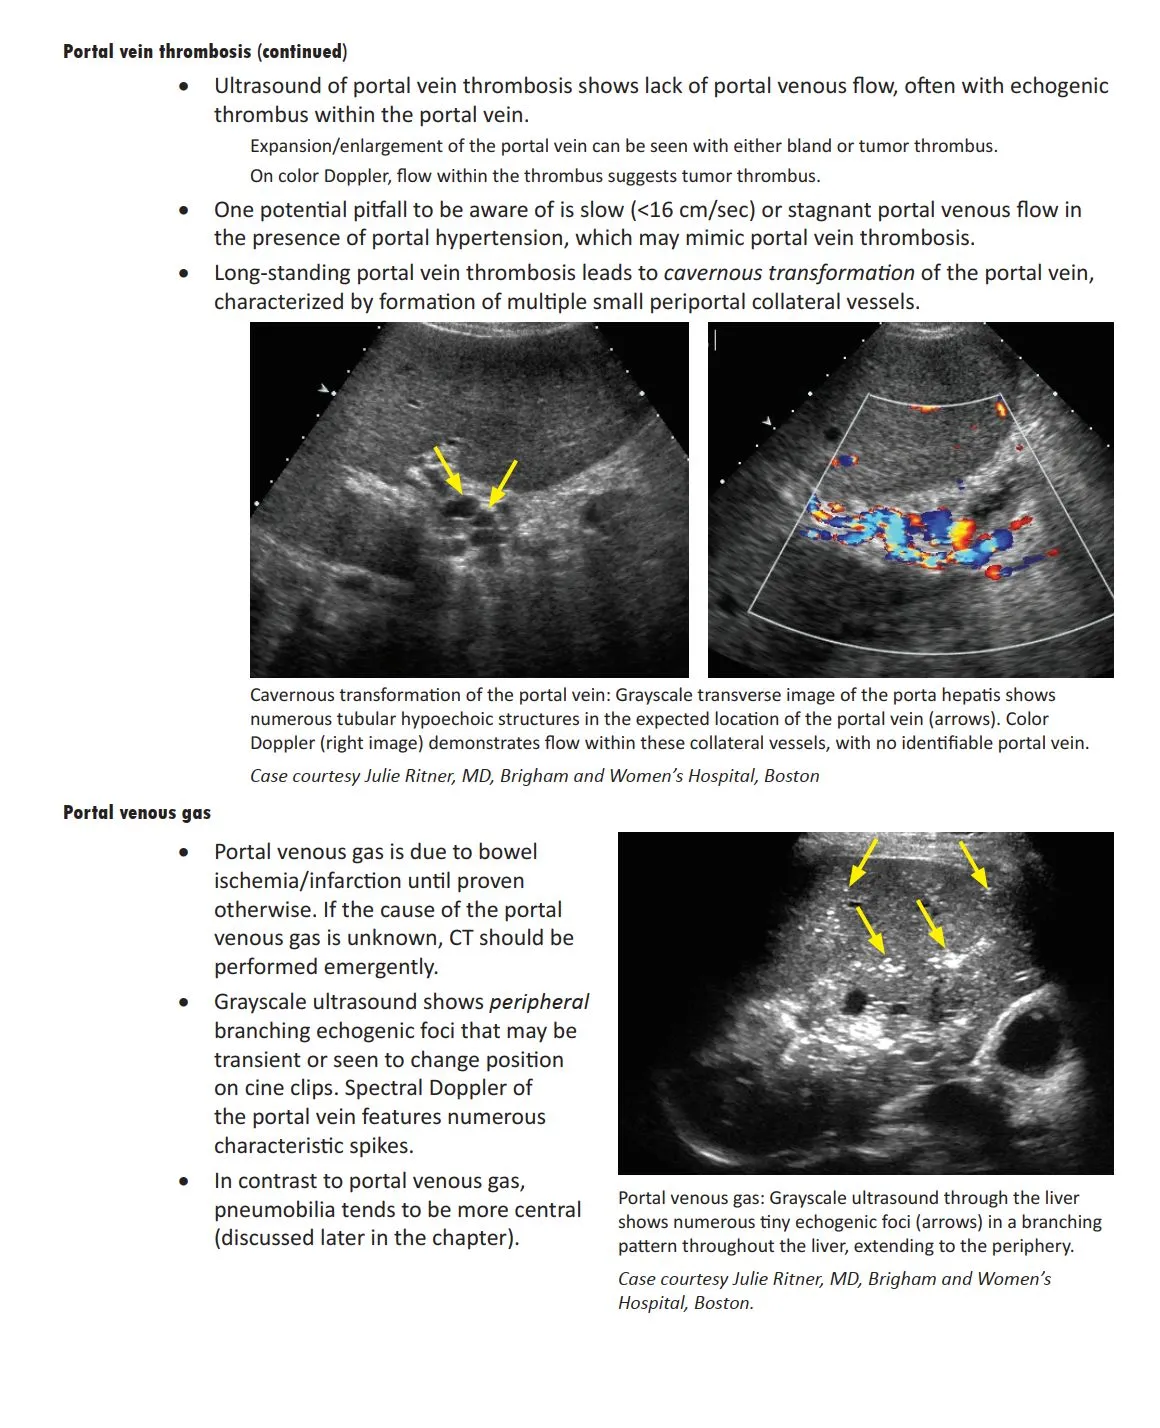

Long-standing portal vein thrombosis leads to {{c1::cavernous transformation}} of the portal vein, characterized by formation of multiple small periportal collateral vessels.